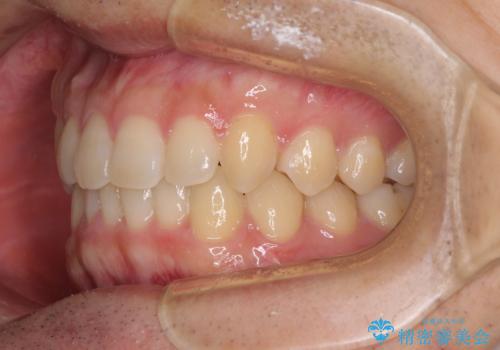

前歯の咬み合わせとデコボコを解消 インビザラインによる矯正治療

- 上下前歯のデコボコと深い咬み合わせを気にして来院された患者様です。

インビザラインによる上下歯列の拡大と、IPR(歯と歯の間を削る)にるスペースの獲得により、前歯のデコボコとディープバイトを改善することとしました。

もう少し下の前歯を整えたかったのですが、患者様の治療を早く終了させたいという希望により、細かい叢生を残しての終了となりました。